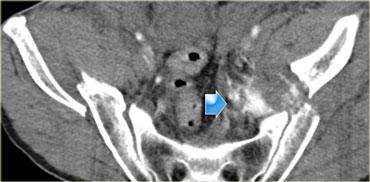

Bên trái là hình ảnh của một nam giới 65 tuổi bị xe ô tô đâm ở tốc độ vừa phải.

Mất ý thức trong 2 phút.

Đặt thông tiểu Foley và phát hiện đái máu đại thể.

Phim X-quang cho thấy gãy xương mu di lệch vừa với các mảnh xương nhọn ở vùng bàng quang.

Bên trái là hình ảnh CT chấn thương thường quy.

Nhận xét các dấu hiệu hình ảnh?

Có hình ảnh gãy xương chậu di lệch với một mảnh xương nhọn hướng về phía bàng quang.

Có dịch trong khoang trước bàng quang (khoang Retzius).

Bên trái là một trường hợp khác để minh họa lý do tại sao không nên bơm thuốc cản quang vào bàng quang cùng lúc với tiêm thuốc cản quang tĩnh mạch.

Câu hỏi tiếp theo được đặt ra là liệu chúng ta có nên thực hiện thêm CT bàng quang cản quang hay không?

Câu trả lời cho câu hỏi thứ nhất là: nếu thuốc cản quang đã được bơm vào bàng quang ngay từ đầu cuộc khảo sát, chúng ta sẽ khó phân biệt liệu thuốc cản quang quan sát được là do vỡ bàng quang hay do chảy máu động mạch đang hoạt động.

Vì không có thuốc cản quang nào được bơm vào bàng quang, nên rõ ràng đây là hình ảnh chảy máu động mạch.

Thứ hai, do mức độ thoát mạch rất lớn, bệnh nhân này cần được thuyên tắc mạch (embolisation) ngay lập tức mà không được trì hoãn thêm.